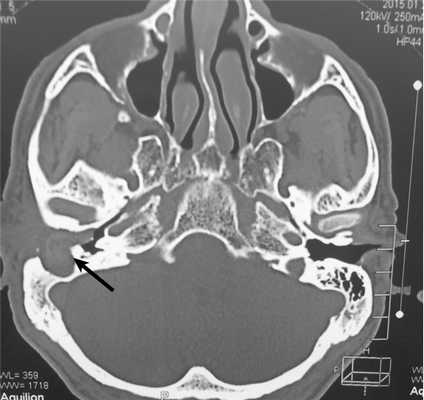

Пациент Б., 61 года, обратился с жалобами на постоянное гноетечение из правого уха, снижение слуха на это ухо. Из анамнеза известно, что с детства отмечались частые обострения правостороннего наружного отита, по поводу чего проводились неоднократные курсы консервативного лечения. При отомикроскопии: правый наружный слуховой проход обтурирован объемным округлым образованием, исходящим из задней стенки, которое стало обозримо только после удаления эпидермально-серных масс. Бактериологическое исследование отделяемого из правого наружного слухового прохода: S. aureus 1·10 5 , E. coli 1·10 3 . При аудиологическом исследовании выявлена правосторонняя смешанная тугоухость. По заключению МСКТ височных костей: патологический субстрат в слуховом проходе и образовавшейся в сосцевидном отростке полости, дефект задней стенки наружного слухового прохода (рис. 1).

Рис. 1. Больной М. МСКТ височных костей. Патологический субстрат заполняет наружный слуховой проход и через дефект задней стенки (стрелка) распространяется в сосцевидный отросток.